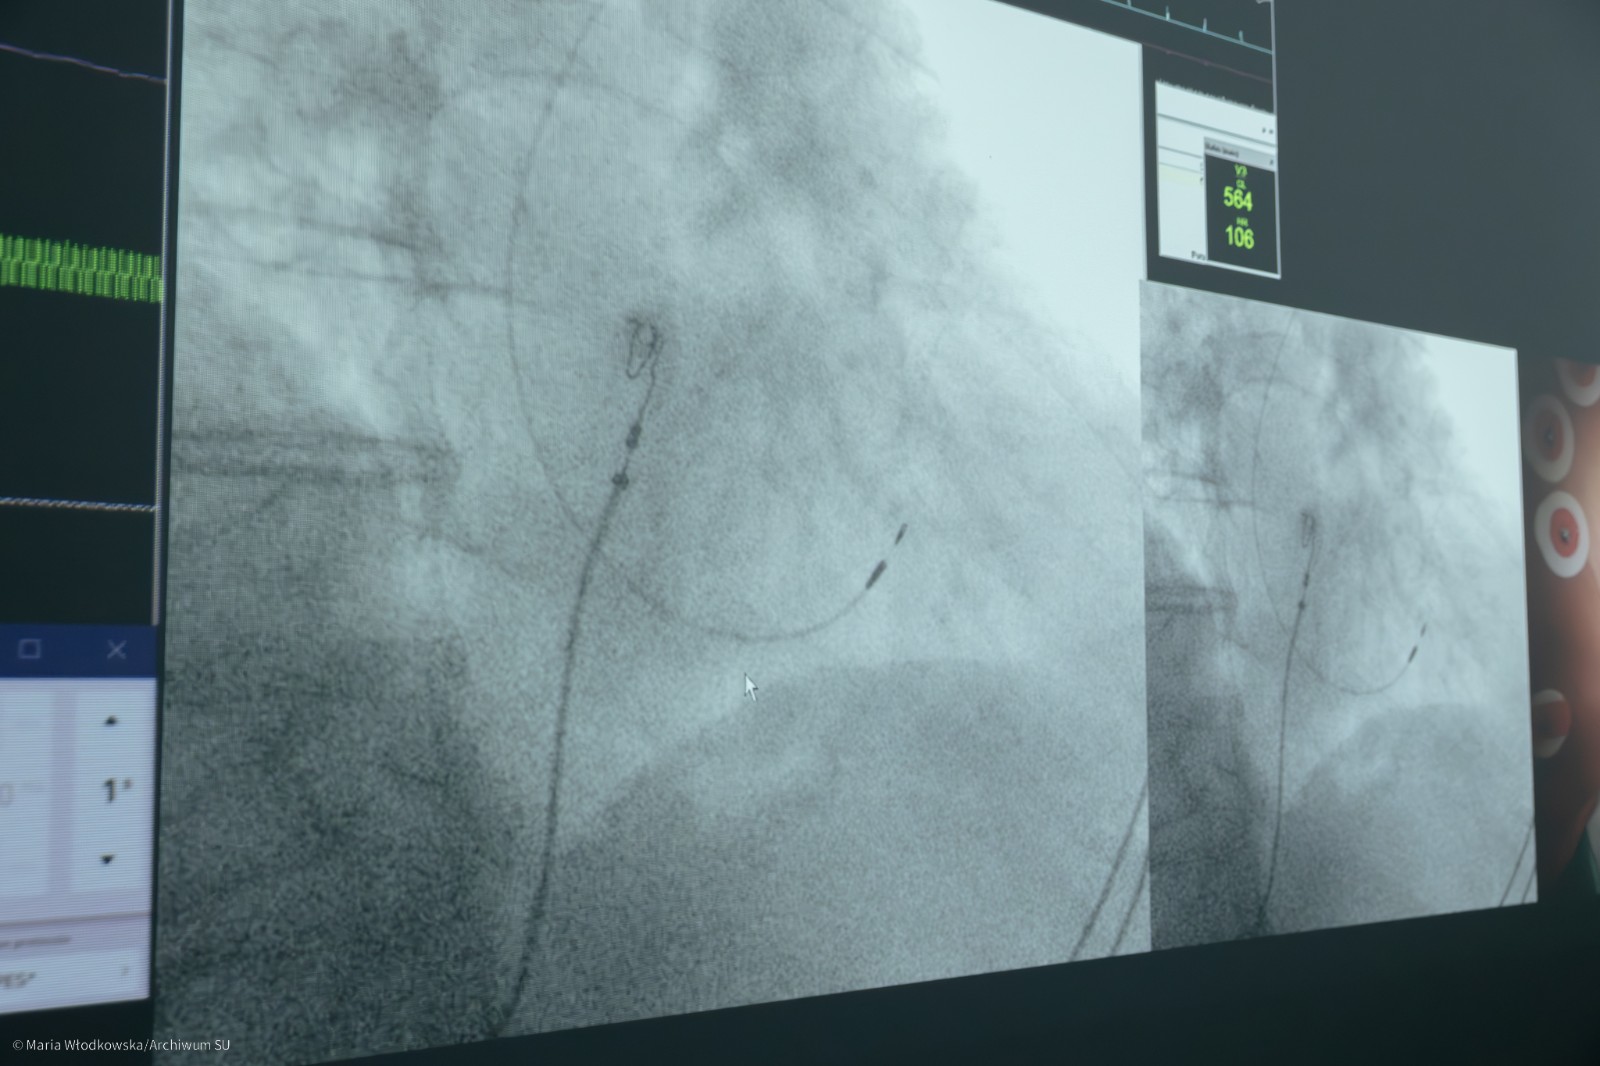

Część praktyczną PPC poprowadzili: prof. Marek Jastrzębski, dr n. med. Paweł Moskal oraz dr n. med. Grzegorz Kiełbasa. Ich doświadczenie i wiedza pozwoliły uczestnikom warsztatów zobaczyć, jak najnowsze techniki stymulacji fizjologicznej są stosowane w codziennej praktyce klinicznej.

Warsztaty z zabiegami wykonywanymi na żywo w Pracowni Elektrofizjologii , podlegającej pod O/K Kardiologii i Elektrokardiologii Interwencyjnej oraz Nadciśnienia Tętniczego są najstarszymi tego typu warsztatami w Polsce, Europie, USA. Od 2018 roku stały się kluczowym miejscem edukacji dla kardiologów z całego globu, prezentując najnowsze techniki stymulacji fizjologicznej serca w praktyce klinicznej. Do tej pory uczestniczyło w nich ponad 300 lekarzy z Polski, Europy, Afryki i Azji, którzy wykorzystują zdobytą wiedzę w praktyce, poprawiając wyniki terapii u pacjentów z zaburzeniami rytmu serca.